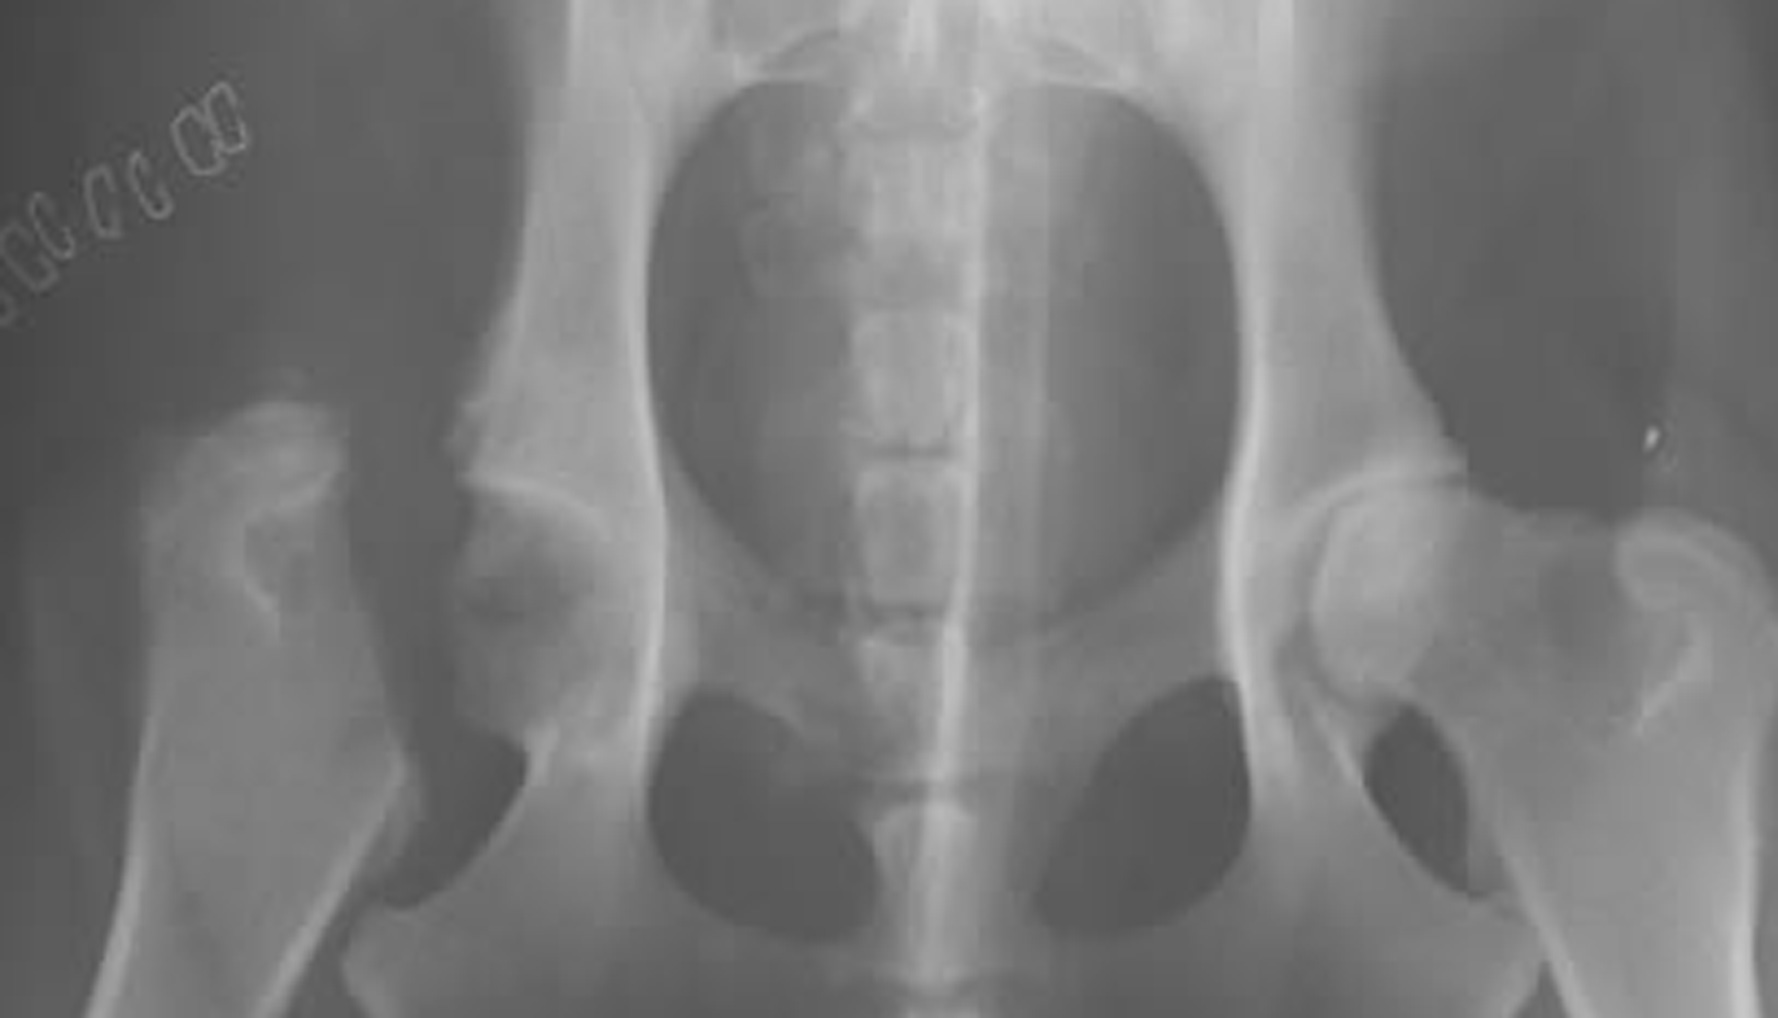

During the FHO surgery, the surgeon will remove the femoral head leaving the socket portion of the hip empty. Your dog's leg muscles will initially hold the femur in place as scar tissue develops between the femur and acetabulum.